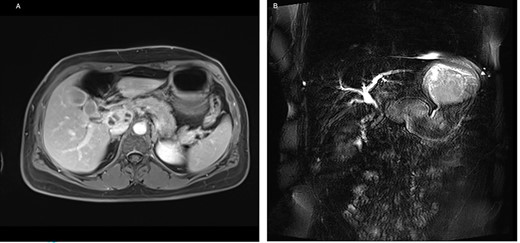

A 53-year-old female of Indian origin, resident in Switzerland for 20 years, presented with diffuse abdominal pain, nausea and meteorism in the primary care consultation. After an initial workup with blood tests and ultrasound (US), a CT of the abdomen was performed (Fig. 3), which revealed enlarged, central necrotic lymph nodes adjacent to the common bile duct (CBD) and the pancreatic head. The enlarged lymph nodes caused an obstruction of the CBD. The patient was referred to our institution for further diagnostic tests.

CT with contrast (A) coronal view and (B) axial view: cystic solid mass in the region of the hepatic hilus with unclear association to the head of the pancreas.